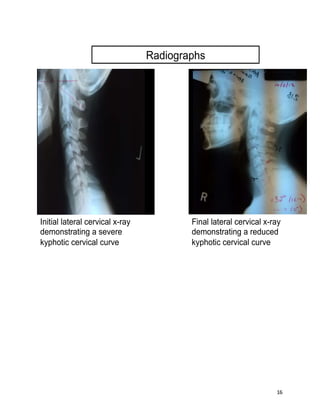

Radiographs

Initial lateral cervical x-ray

demonstrating a severe

kyphotic cervical curve

Final lateral cervical x-ray

demonstrating a reduced